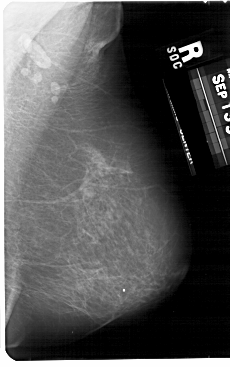

A_1676_1.RIGHT_MLO

RIGHT_MLO LINES 5491 PIXELS_PER_LINE 3436 BITS_PER_PIXEL 12 RESOLUTION 43.5 NON_OVERLAY